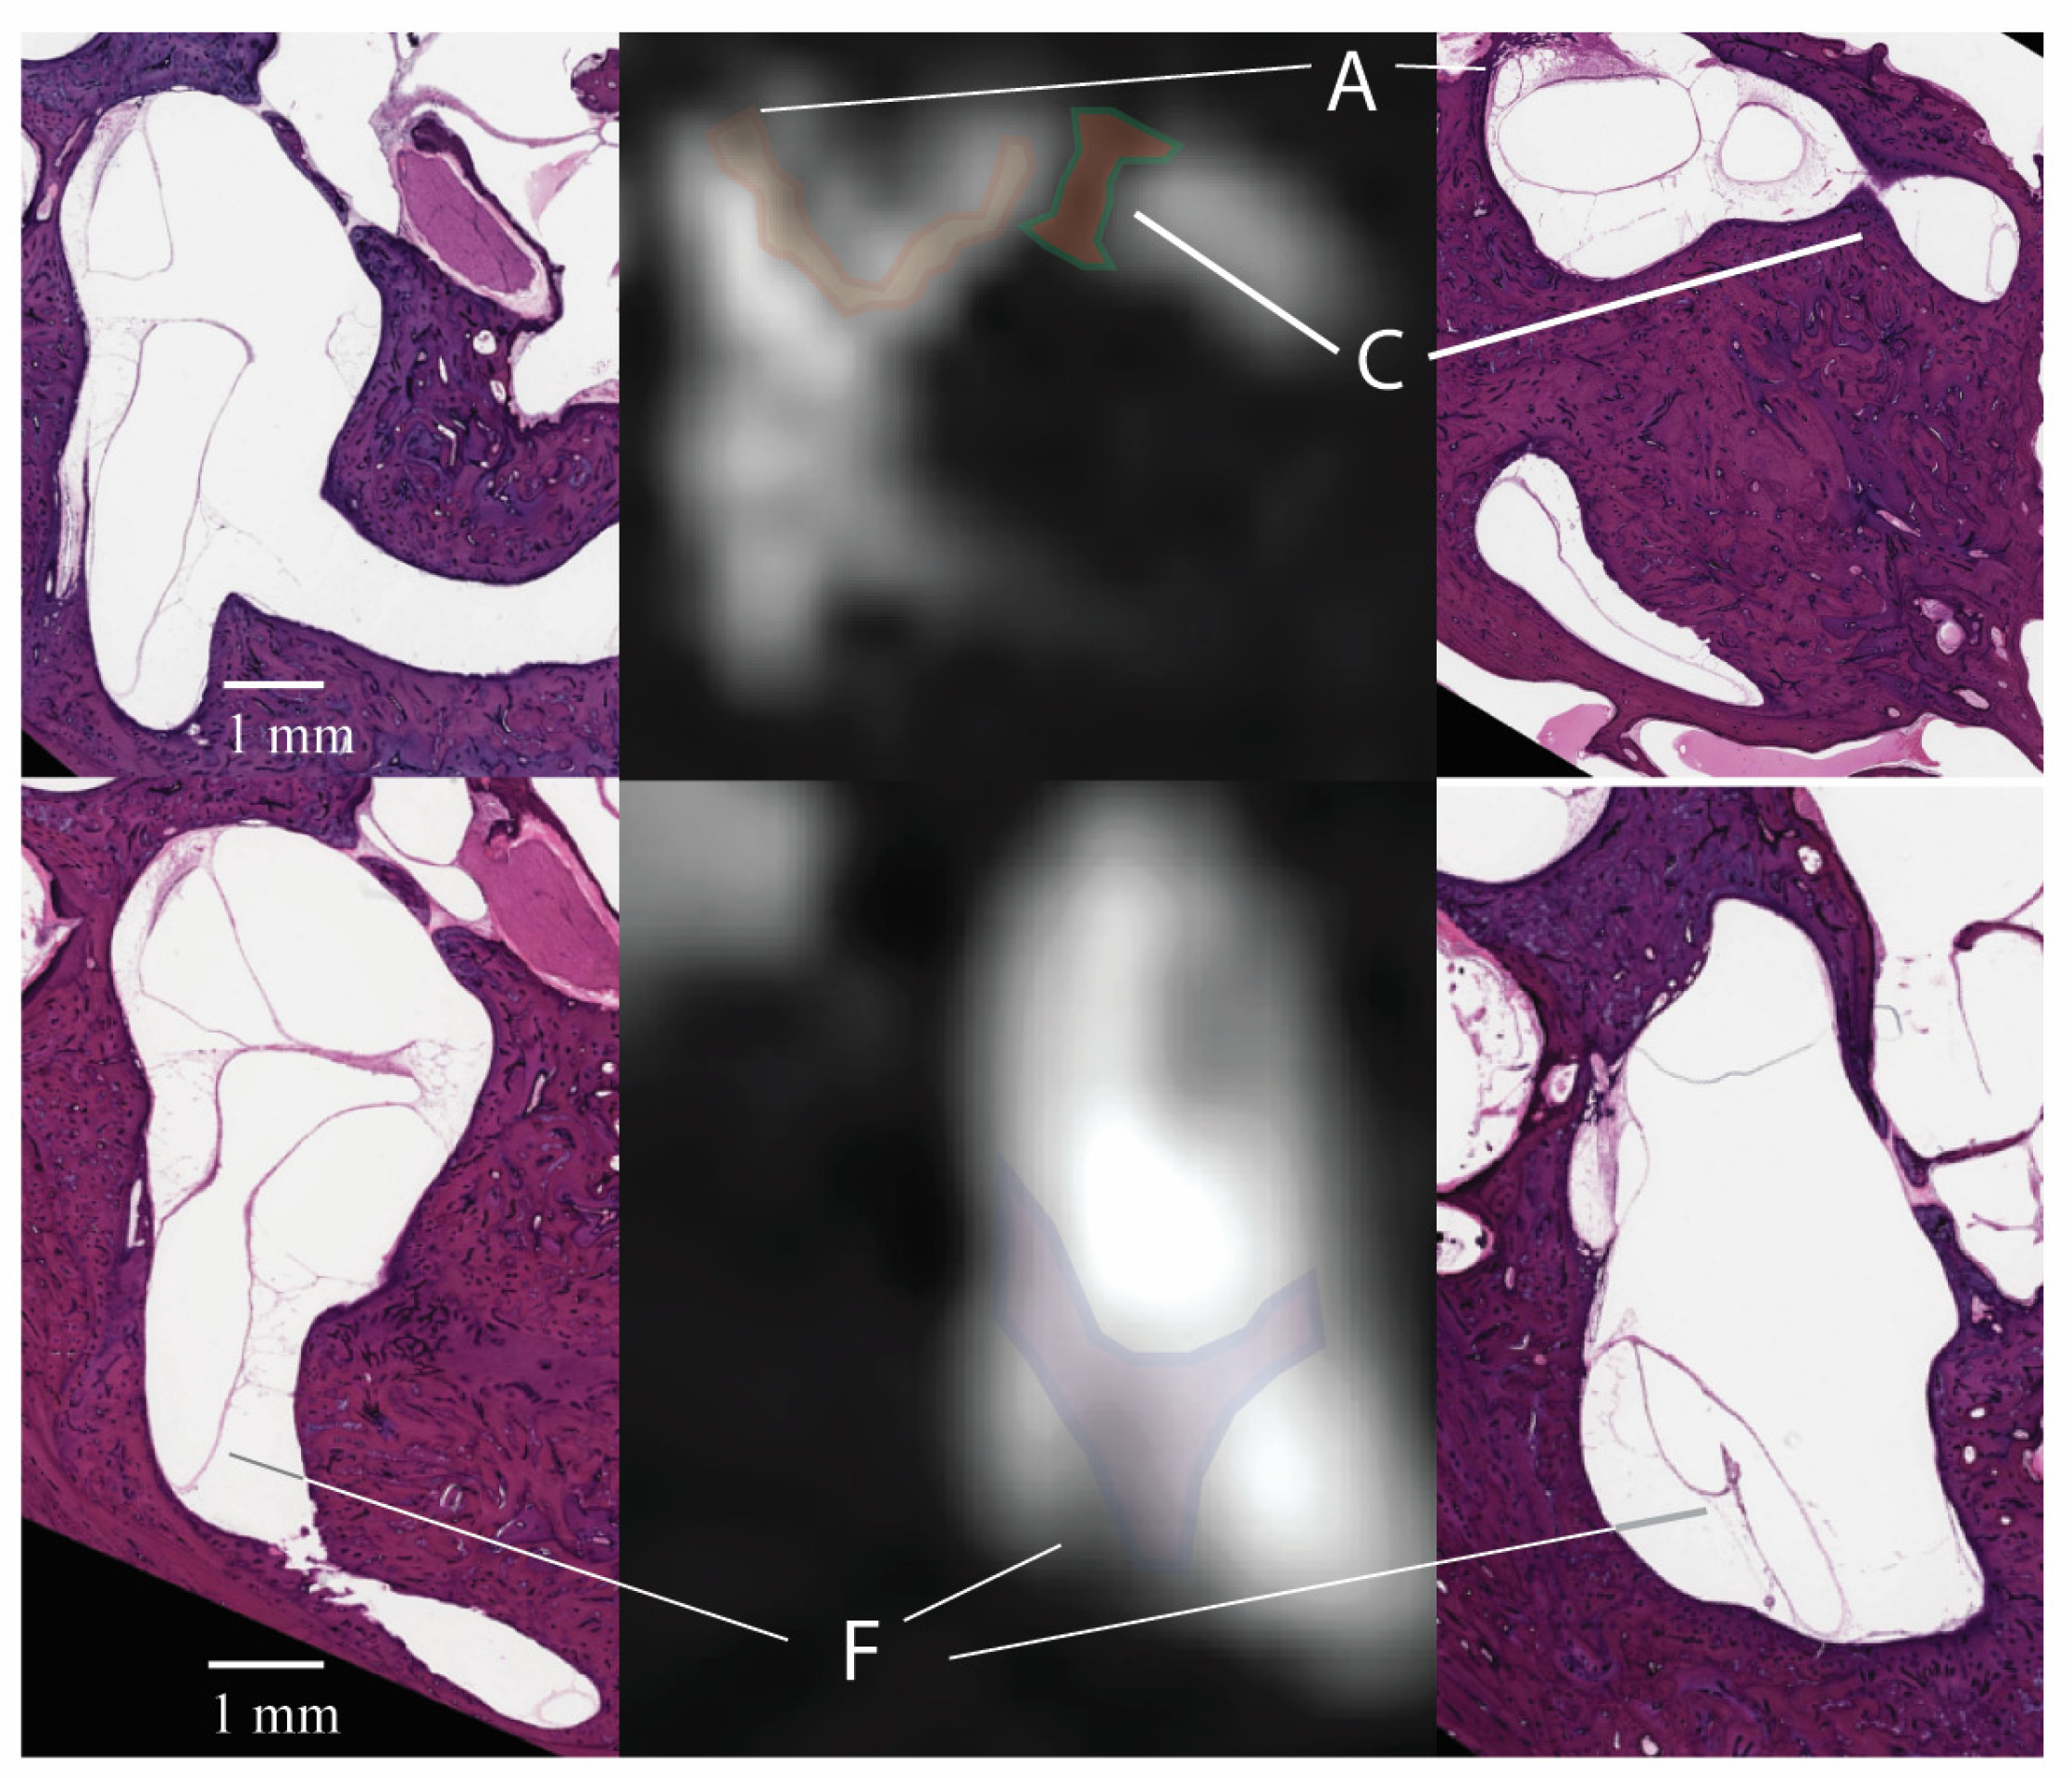

3.1. Signal Areas in the Inner Ear

| Regions of Low Signal Intensity within the Inner Ear (n) | ||||||||||

|---|---|---|---|---|---|---|---|---|---|---|

| A | B | C | D | E | F | G | H | I | ||

| Right ear | Reader 1 | 8 | 6 | 6 | 7 | 9 | 9 | 8 | 10 | 10 |

| Reader 2 | 8 | 6 | 5 | 7 | 9 | 9 | 8 | 9 | 10 | |

| Left ear | Reader 1 | 10 | 7 | 4 | 7 | 10 | 10 | 8 | 10 | 10 |

| Reader 2 | 10 | 7 | 4 | 7 | 10 | 10 | 8 | 10 | 10 | |

| Regions of Low Signal Intensity (n) | |||||||||

|---|---|---|---|---|---|---|---|---|---|

| A | B | C | D | E | F | G | H | I | |

| Right ear | 27 (90.0%) | 21 (70.0%) | 10 (30.3%) | 22 (73.3%) | 28 (93.3%) | 29 (96.7%) | 24 (80.0%) | 29 (96.7%) | 30 (100%) |

| Left ear | 28 (93.3%) | 21 (70.0%) | 14 (46.7%) | 25 (83.3%) | 26 (86.7%) | 29 (96.7%) | 26 (86.7%) | 30 (100%) | 30 (100%) |